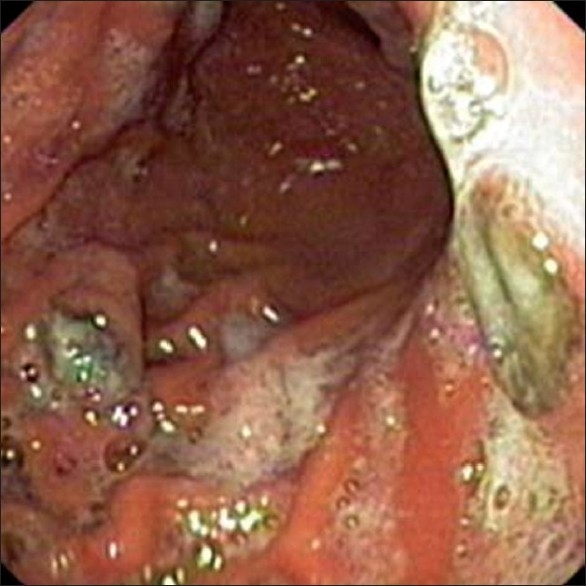

The complete blood counts, and liver and renal function tests were normal. A contrast-enhanced computerized tomography (CT) scan of the abdomen showed marked hepatomegaly with multiple hypodense lesions in both lobes of the liver. Gastroduodenoscopy revealed two round elevated lesions with surface ulceration and black base-one over the lesser curvature and another over the greater curvature. [1]Two other tiny black-colored flat spots were seen over the mucosa of the body.

| Figure 1 Gastroscopy showing elevated lesions in the stomach with a black base and surface ulceration